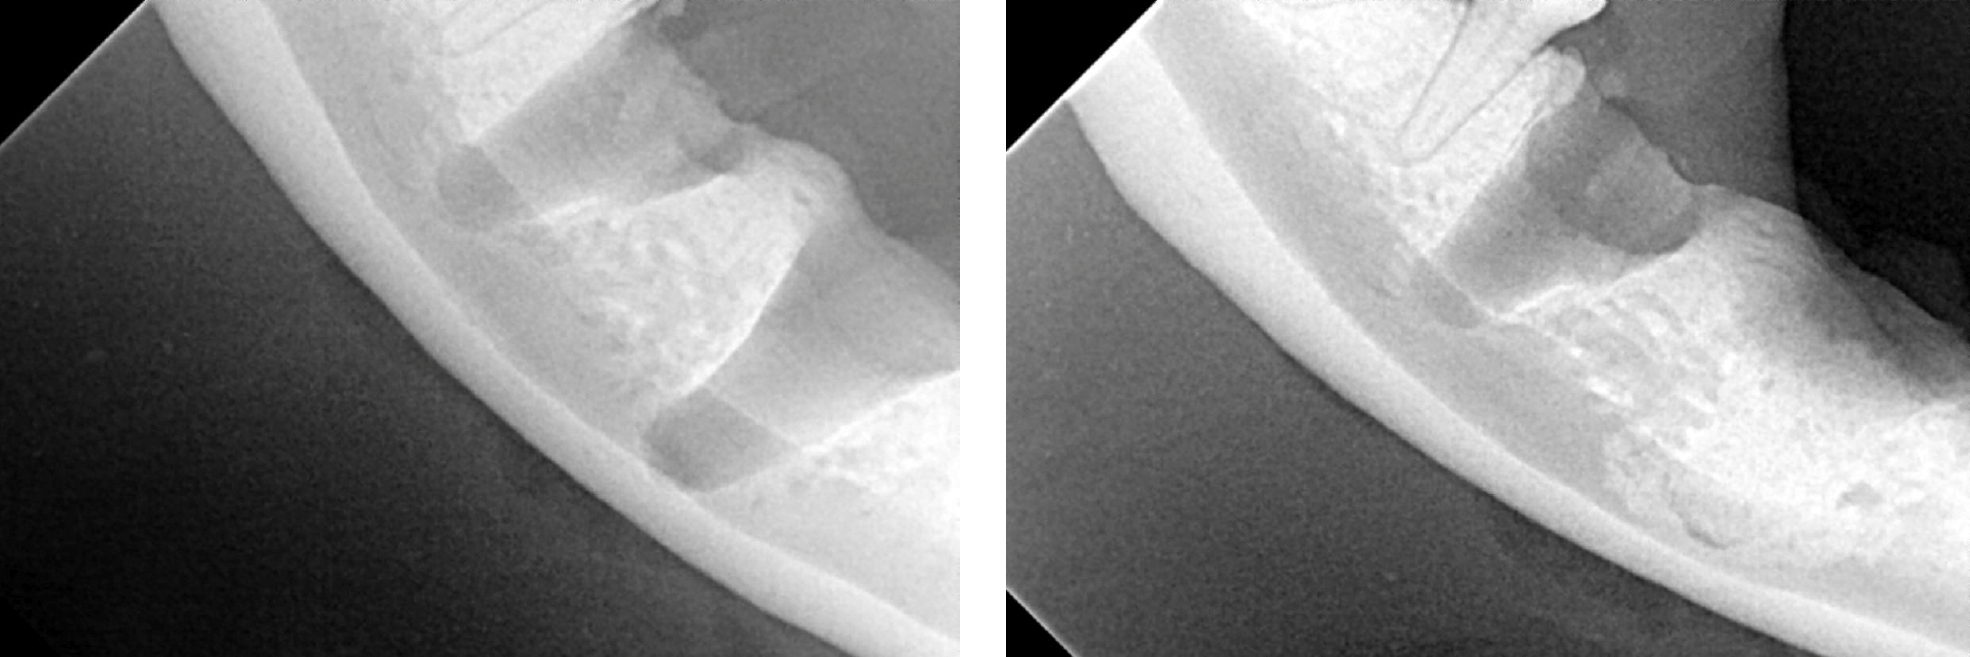

Below: CBCT Hard tissue reconstruction

Below: High intensity CBCT Image

Below: Bone loss affecting upper left canine tooth

Below: Imaging of both sides of the lower right 4th premolar

Furcation exposure level 2 indicating bone loss under the crown